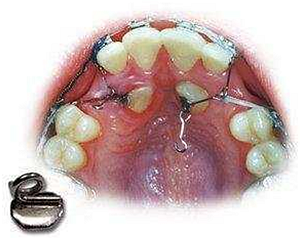

什么是 牙齒牽引?

牙齒牽引就是正牙過程中的一個步驟。是要把長的不規(guī)范的牙齒借助外力,牽引到正確的地方。

牽引牙會不會掉?

像出現(xiàn)乳牙下面還有一顆恒牙的情況,是必須拔掉乳牙,把恒牙牽引出來,不然時間長了恒牙出不不來,就容易形成牙囊腫,而牙齒牽引出來,并不會使他的牙齒與牙槽骨分離,所以不需要擔(dān)心牙齒會掉!

而牙齒并沒有我們想象的那么脆弱,在做牙齒矯正過程中可能牙齒會比較松動,但是不會引起牙齒脫落的情況,具體如何牽引和實施的方案,應(yīng)根據(jù)個人情況由醫(yī)生制定。